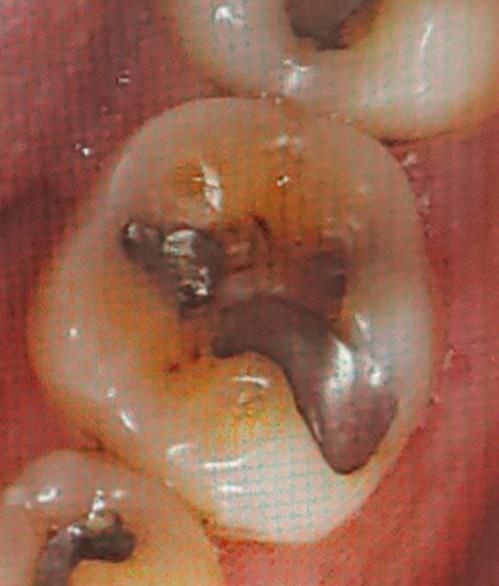

레진 인레이 크라운 어느 것이 좋을까요?

아래 어금니 바로 앞에 치아입니다.

통증은 없습니다.

지난번에 엑스레이를 잘못 올려서 다시 올립니다. 엑스레이상으로 볼 때 많이 안좋은가요?

아말감, 레진, 인레이, 크라운 중에서 어느 것을 해야되나요?

아말감, 레진, 인레이가 치아를 흔히 말해 떼운다고 하는 한 묶음의 치료 방향이고 크라운은 결이 다른 치료입니다.

위 상태로 봐서는 기존 아말감이 굉장히 깊게 수복되었고, 아말감이 깨져나가면서 하방 이차충치가 의심됩니다. 이런 경우 치수염이 유발되어 신경치료 가능성도 있긴하나 현재 증상이 없다면 간접신경치료 내지는 부분신경치료도 가능할 것 같습니다. 그렇게 해서 떼울 수 있다면 이제 재료는 선택입니다. 아말감으로 다시 해도 되고 아니면 레진이나 금/세라믹/레진 인레이를 선택하셔도 됩니다. 요샌 아말감은 거의 안씁니다. 저렴하게 하고자 한다면 레진으로 떼우는 것도 가능할 것 같습니다.

반면 신경치료를 한다면 일단 신경치료하고 그 다음에 치아 상태보고 크라운으로 씌울지 결정합니다.